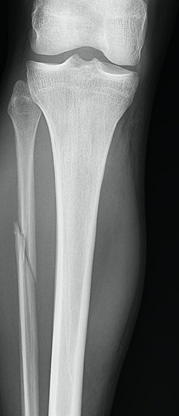

Obtaining images at the initial visit is important to rule out a Maisonneuve fracture. Plain radiographs are vital as they can identify fibular fractures, fibular shortening, and any abnormal spacing between the tibia and fibula caused by syndesmotic disruption. Traditionally, ankle radiographs are taken in anterior-posterior (AP) view, stress view (abduction and external rotation), mortise view, and lateral view (Figures 3a-d). It is necessary to acquire AP and lateral radiographs of the knee with tibial and fibular views to determine the extent of the fibular fracture (Figures 4a-b). When reviewing the radiographs, it is important to measure the tibiofibular clear space, medial clear space, and tibiofibular overlap. The tibiofibular clear space is measured at 1 cm above the talus and measures the distance between the medial border of the fibula and the lateral border of the tibia. Typically, the tibiofibular clear space is less than 5-6 mm on the AP and mortise views. Anything greater than 10 mm is diagnostic of a syndesmotic injury.